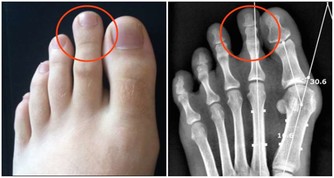

菠蘿蛋白酶是一種蛋白質消化酶,使這種熱帶水果成為最有效的抗炎食品之一。研究表明,吃菠蘿可以減輕膝關節骨性關節炎和類風濕性關節炎的疼痛,降低腕管綜合症患者的腫脹。

研究人員發現,那些食用橙子、橘子和橙色水果,包括杏子和油桃的人,不太可能患有炎症性關節疾病。每天只需要吃一兩份這些水果,就能見到效果。